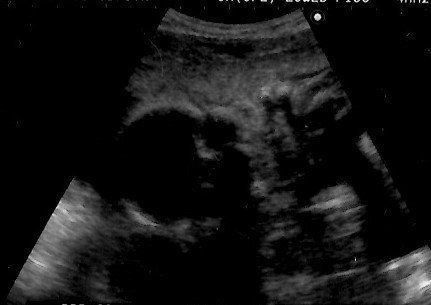

妊娠40週目のエコー写真 羊水の状態が悪くなり、計画出産が決定

出産の兆候がないまま予定日を過ぎ、赤ちゃんの体重はとうとう4000g越えに。病院での検査の結果、羊水の状態が良くないことがわかり、すぐに入院~出産することが決まりました。今思うと、当時は出産後の大変さを予想できないまま、楽観的な気持ちで病院に向かっていた自分が本当に情けないです。でも、もしその後の大変さを知っていたなら、おそらく出産に挑むことはできなかったかもしれないな、とも思います。

妊娠40週目のエコー写真 帝王切開で出産

入院後は次々と襲ってくる激しい陣痛に10時間以上耐えました。そして何度も検査した結果、医師の判断で帝王切開をすることが決定。夫は看護師に促されるままに同意書にサインし、私は即手術台へ。あっという間に4100g、54cmのビッグサイズのわが子が、妊娠40週と5日目に誕生しました。初めて見たわが子の顔は、3Dエコー画像で見たものとそっくり。夫婦で笑ってしまいました。